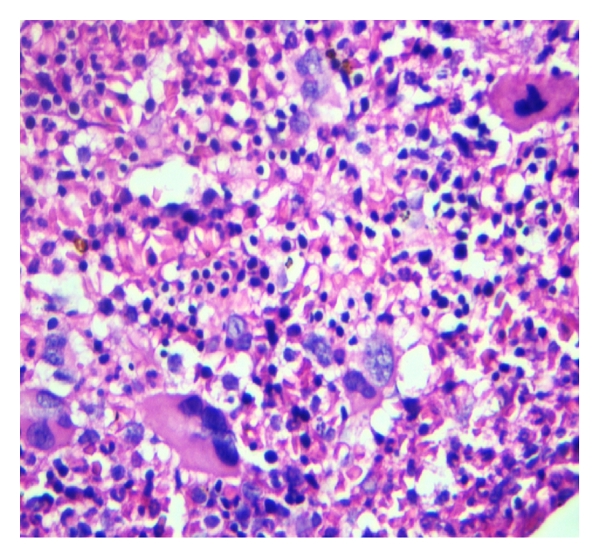

A month following red cell transfusions and treatment of the deficiencies, blood counts were as follows: Hb 10.5 g/dL, WBC 37.5 × 109/L, platelets 75 × 109/L, and reticulocytes 4.8%. BM biopsy revealed mostly hypercellular areas with increased M : E ratio. Megakaryocytes were increased in number, exhibiting highly pleomorphic nuclei and bizarre forms. Many nuclei had cloudy, balloon-like appearance. Reticulin fibrosis of grade 2/4 along with few distended marrow sinusoids was evident (Figures 2(b), 2(c), and 2(d)). These features characterized the cellular phase of PMF, presenting with combined deficiencies of iron and folic acid. JAK2 mutation was negative and karyotype was normal. This case was referred to oncology for further management of MPN.